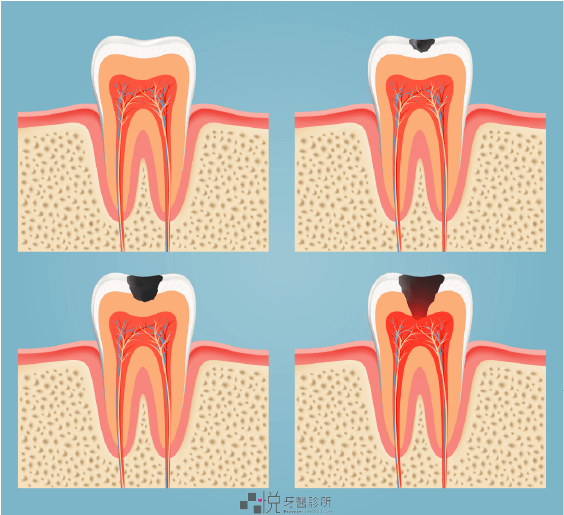

蛀牙隨時間變化的進程

蛀牙的進程

初期蛀牙:不易察覺

蛀牙的初期並沒特別的感受,牙齒最外層的珐瑯質常常是完整或者有輕微的脫鈣變白,有時憑著肉眼不一定可以看到蛀洞;牙齒鄰接面的蛀牙更難察覺,大多需要照 X 光幫忙確認檢查

中期蛀牙:牙齒敏感

當蛀牙持續進展,會到下方的象牙層,此時有的人會感覺到吃冰的、甜的、酸的很敏感

嚴重蛀牙:牙髓腔感染

如果不處理接下來就會到達下方的牙髓腔,牙髓會因為細菌感染而導致壞死

同時,細菌可以從牙髓腔的空間往下到牙根尖,進而擴散至四旁的牙周組織或骨頭導致發炎,可能會有比較劇烈的疼痛不適,甚至鄰近牙肉臉頰腫脹或化膿